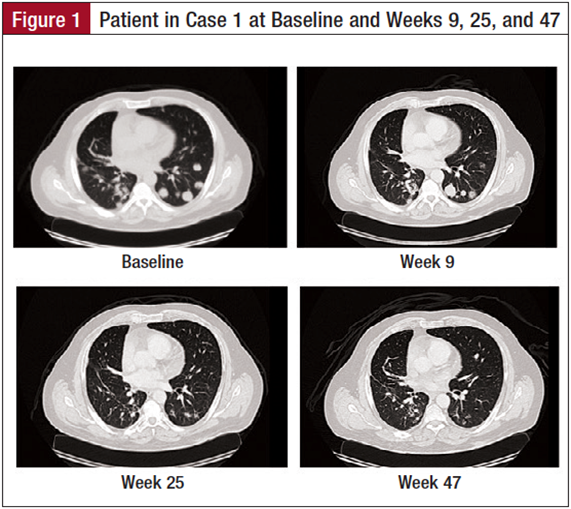

The patient is a 66-year-old man with a medical history of hypertension and a remote smoking history who initially palpated a mass on the left side of his neck in July 2008 (Figure 2). He was referred to an ear, nose, and throat specialist, and was noted to have a mass overlying and possibly involving his left parotid gland. The patient underwent a fine needle aspiration of the lesion, but pathology was nondiagnostic. He subsequently underwent a neck magnetic resonance imaging, which showed the lesion to be localized to the left parotid. In October 2008, he underwent a left total parotidectomy and left modified radical neck dissection. Pathology from the resection was consistent with a 3.7-cm invasive, high-grade, basaloid squamous cell carcinoma involving the parotid gland and periparotid soft tissue. Evidence of malignancy was seen in the deep parotid tissue as well as in 1 of 5 dissected lymph nodes.

There was evidence of perineural invasion by the tumor. The tumor was positive for p63 and KER 5/6, and negative for S100, GFAP, EMA, CEA, and CD117. In the adjuvant setting, the patient received concurrent carboplatin (Paraplatin), docetaxel (Taxotere), and radiation. He completed his course in January 2009, underwent surveillance scans after completion of his concurrent therapy, and did well until February 2011. Surveillance images at that time noted a lesion in the lung and a lytic lesion in the iliac bone. In July 2011, he underwent a percutaneous needle biopsy of the right iliac lesion with pathology again being consistent with metastatic carcinoma consistent with the patient’s history of basaloid squamous cell carcinoma. The tissue was positive for p63, SMA, and pancreatin AE1/AE3, and negative for Vimentin, S100, CD117, CK5/6,andEMA.

Given the stage IV diagnosis, the patient resumed chemotherapy with vinorelbine shortly after the biopsy. After 2 cycles, scans showed disease progression, and therapy was changed to carboplatin and docetaxel with continued progression. He then received bevacizumab and everoli­mus with no improvement in his disease. Subsequent therapy with cetuximab also did not provide benefit. Upon progression, he was enrolled in a clinical trial with a novel vascular endothelial growth factor inhibitor that provided stabilization of his disease for 4 months, after which his disease began to progress.

In September 2013, the patient presented for consideration of an immunotherapy clinical trial. He was subsequently enrolled in an anti–PD-L1 antibody trial that did not mandate PD-L1 protein expression testing. He underwent a fresh biopsy for the trial, but his PD-L1 protein expression was unknown at the time of his enrollment. Baseline scans prior to initiating the trial indicated evidence of left mastoidectomy and radical left neck surgery. There was evidence of numerous pulmonary nodules and pleural nodularity bilaterally. The largest pulmonary nodule measured 5.1 cm. There was a small right pleural effusion, and there was also evidence of a 5.2-cm lytic and sclerotic lesion involving the right ilium.

The patient began on the anti–PD-L1 antibody with his first infusion in December 2013. His first scans 6 weeks after enrolling into the study indicated evidence of stable disease with minimal shrinkage of his pulmonary lesions. Subsequent scans have shown a dramatic reduction in the size and burden of his pulmonary nodules. His pleural effusion has resolved. The patient has been tolerating the therapy well with no side effects. He is continuing to receive the anti–PD-L1 antibody every 2 weeks with continued evidence of tumorshrinkage9monthsafterenrollinginthestudy.[17]